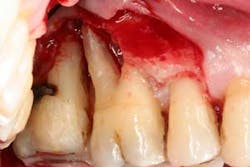

Figures 5a and 5b: Osseous surgery in the upper right quadrant with debridement of root surfaces and then regeneration.

Briefly, during osseous surgery, the upper right molars were treated with a combination of autograft and platelet-derived growth factor/Beta-tricalcium phosphate along with a porcine collagen graft (figures 5a and 5b). The upper left osseous surgery consisted of the same treatment (figures 6a and 6b), but also included the extraction of a hopeless tooth No. 15. Once again, the anterior osseous surgery consisted of the same regenerative materials as the former surgeries but with the addition of a porcine soft-tissue graft (figures 7a, 7b, and 7c). After the initial healing phase, the patient was placed on a strict home-care regimen and was seen every eight to 12 weeks for hygiene recare. The patient maintained excellent hygiene throughout the five-year follow-up period.